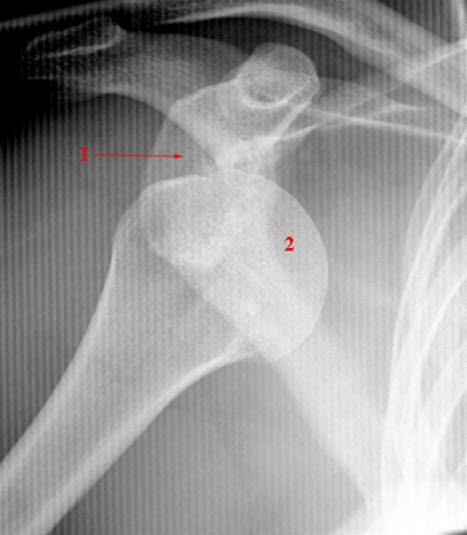

Et ledd som er ute av stilling, dislokert, kan skyldes en sterk kraft som vrir et av bena i leddet ut av sin normale posisjon. Slike skader er vanligst i skulder, kjeve og fingre - en dislokert tommel er en hyppig skiskade. Leddet får da en annen form enn normalt. Det kan også foreligge hevelse og bloduttredelse rundt leddet. Et dislokert ledd i ryggen kan være en alvorlig tilstand fordi det kan skade ryggmargen. I noen tilfeller kan en skulder eller hofte ut av ledd skade nerver i området.